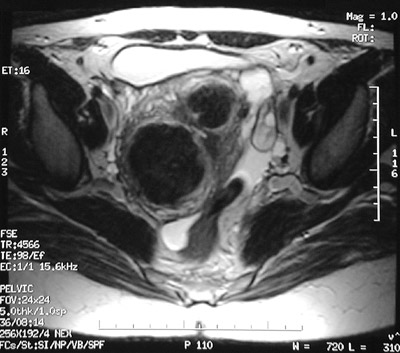

These axial MRI scans of the pelvis show a large nodular uterus containing leiomyomata. The T2 weighted FSE image above and the T1 weighted SE image below both reveal a larger as well as a smaller mass involving the uterus.